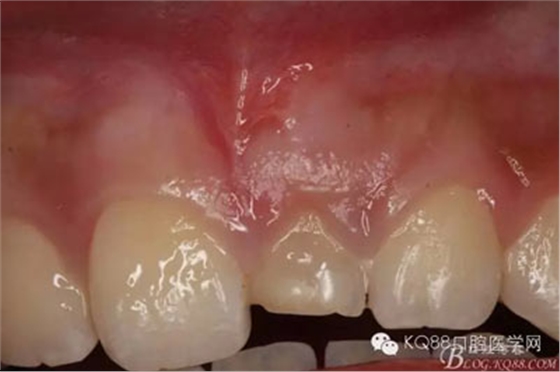

圖3.術(shù)前口內(nèi)片檢查:左乳Ⅰ滯留,21未萌出,22萌出正常